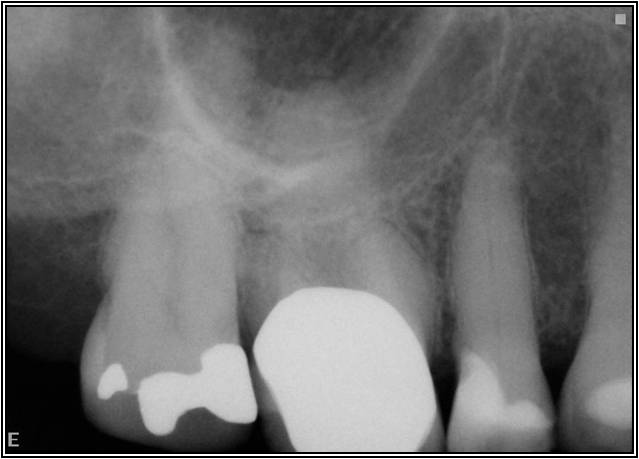

Excellent diagnosis essentially begins with two fundamental components: a doctor willing to listen to the patient’s chief complaint, and proper diagnostic tools. Among the most important tools are a precise periapical radiograph (PA) and bitewing (BW). Although a PA is often enough to provide an accurate portrayal of the patient’s condition, sometimes it alone does not suffice. Figure 1, Figure 2, and Figure 3 demonstrate a case that illustrates this point clearly. Despite two acceptable PAs (Figure 1 and Figure 2), it is difficult to assess the source of the patient’s pain to temperature. However, the BW radiograph Figure 3 provides significantly more clarity than either of the two PAs. The BW depicts localized bone loss (around tooth No. 2), a pulp stone (No. 2), a flat occlusion, numerous calcified canals, multiple restorations in tooth No. 30, and gross decay especially on tooth No. 3, which is the source of the patient’s pain to temperature. In this instance these images depict how much more useful a BW can be than just a conventional PA.